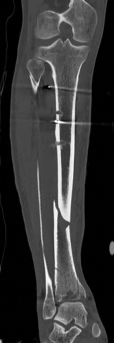

Pre-operative planning is the cornerstone of successful execution in complex pilon-variant tibial shaft fractures. The surgeon must transition from a conceptual understanding of the injury to a concrete, step-by-step surgical blueprint. This begins with high-quality orthogonal radiographs of the entire tibia, ankle, and knee. However, plain films drastically underestimate the degree of articular comminution and central impaction. A fine-cut computed tomography (CT) scan with 2D multiplanar reformats (coronal and sagittal) and 3D surface rendering is absolutely mandatory.

Image

The CT scan allows the surgeon to map the fracture lines, identify the primary articular fragments (Chaput, Volkmann, medial malleolus), and quantify the degree of central die-punch impaction. In an AO/OTA 43C3.3 fracture, where no articular fragment is in continuity with the diaphysis, the surgeon must plan the sequence of reduction. Typically, the fibula is addressed first to restore lateral column length and rotation, provided the fibular fracture is not located at the level of the syndesmosis where fixation might interfere with the lateral surgical approach to the tibia.

Digital templating is utilized to select the appropriate implant. For a fracture extending into the diaphysis, an extra-long anatomical distal tibia locking plate is required. The surgeon must determine whether an anterolateral or medial plate (or dual plating) will provide the optimal biomechanical construct based on the fracture morphology. The trajectory of the distal locking screws must be planned to provide a subchondral raft supporting the articular surface without penetrating the joint space. Furthermore, the availability of bone graft or orthobiologics must be confirmed, as elevating impacted articular segments will leave a metaphyseal void requiring structural support.